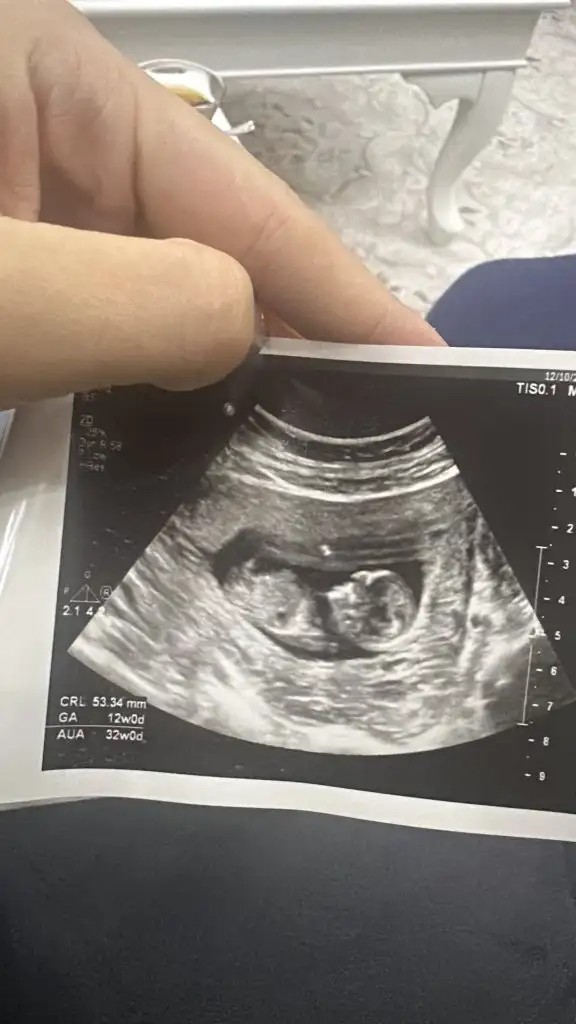

Benim bebişime de tahminde bulunur musunuz burda 22 haftalık filandı sanırım şuan 28 haftalık

• IMG_1175.webp

IMG_1175.webp

19 KB · Görüntüleme: 86

Benim bebişime de tahminde bulunur musunuz burda 22 haftalık filandı sanırım şuan 28

Oyy maşallah, benim tahminime göre kıza benziyor. Hiç bir çıkrıntı göremedim, 22 haftalıkken tok bir görüntü olması lazımdı diye düşünüyorum, aslında 22 haftalıkken söylemeleri lazım, neden söylemediler